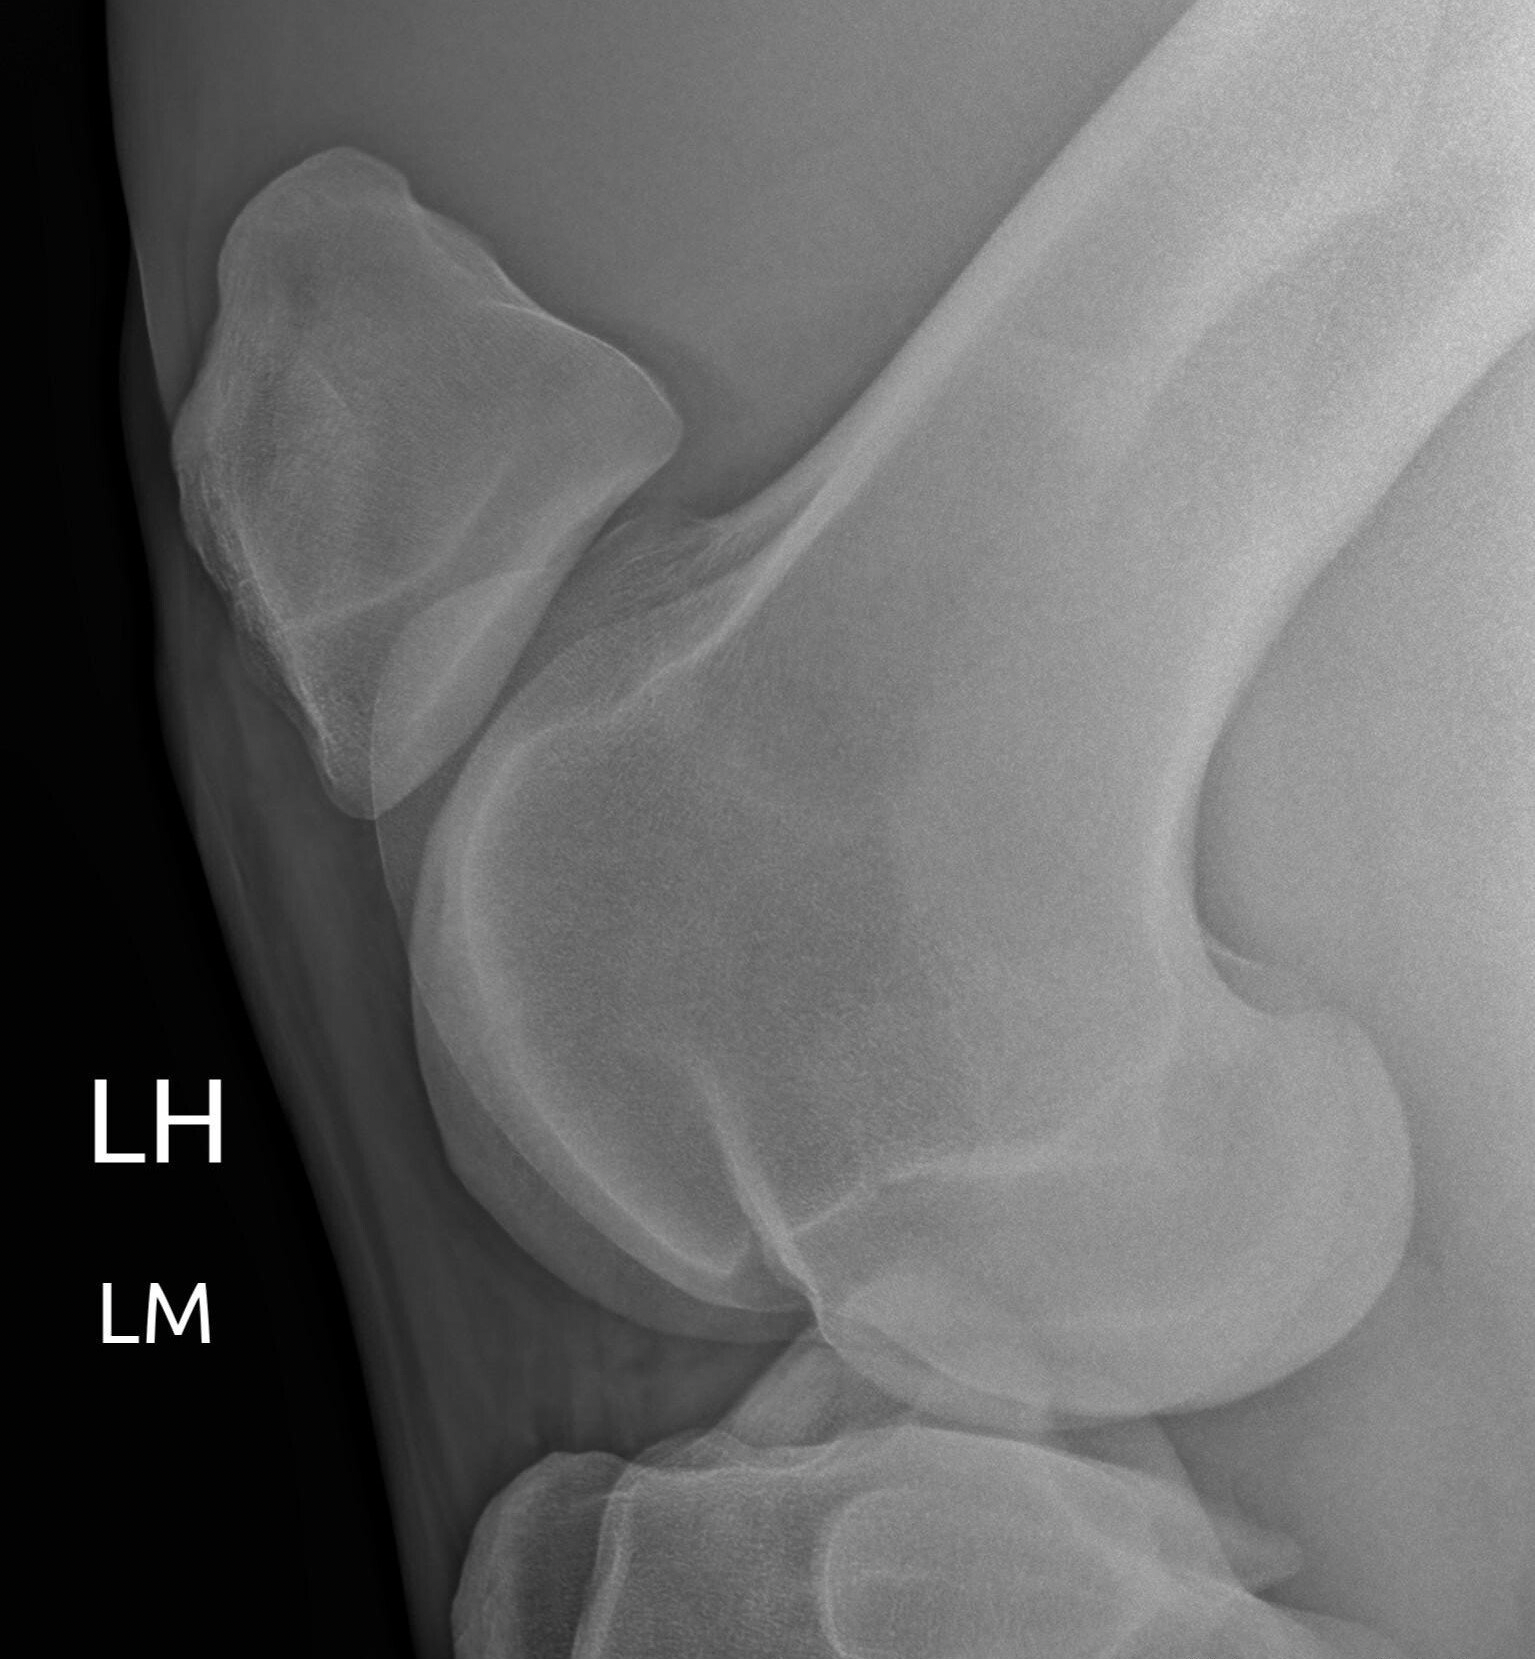

Orthopedic examination

Is your horse limping? Is your horse stiff? Does the horse feel different than normal?

These findings may be one of the reasons why you, as an owner, want to have an orthopedic examination done on your horse.

A good orthopedic examination begins with a comprehensive anamnesis that includes how the problem arose, how long the problem has been going on, what treatments, if any, have already been tried, etc.

The anamnesis is followed by a good clinical examination in which the horse is fully examined and scanned for any joint incidence, swelling at the level of tendons, pain spots, conformation abnormalities, ...

A movement analysis is the next step in the orthopedic research. The horse is examined on the lunge on a hard and a soft surface with additional bending tests. If necessary, this examination is supplemented by a ridden examination

The goal is to find the region where the pain/crushiness is coming from. For a more specific indication of the pain location, local anesthetics are then used.

Once the pain site is localized, medical imaging is applied to arrive at a correct diagnosis and thus to initiate appropriate treatment.